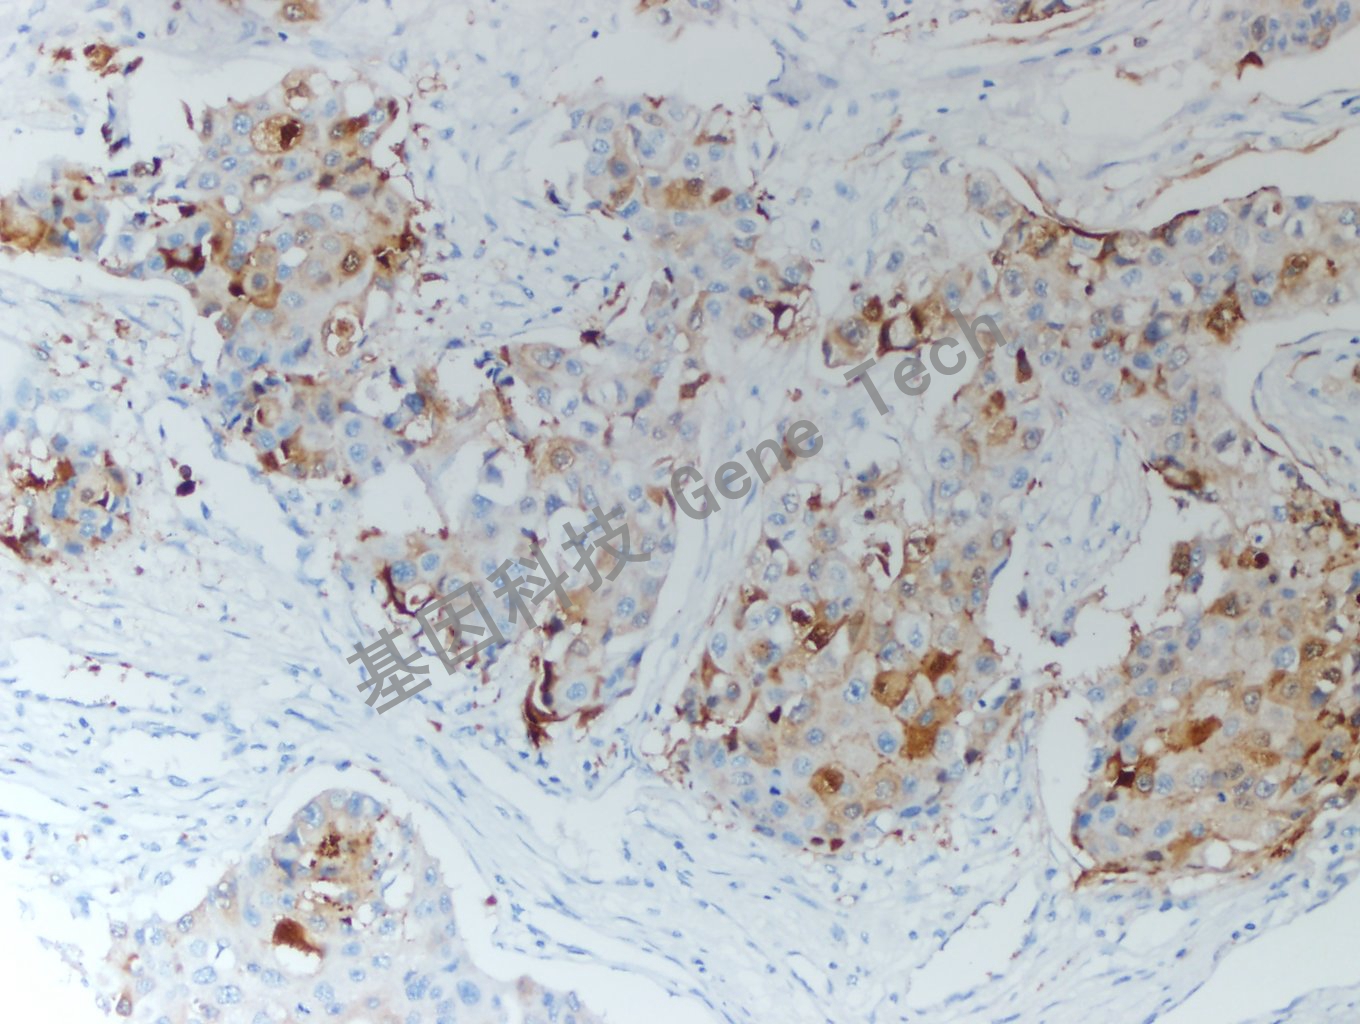

| 乳腺癌石蠟組織,用 HIF-1α(GT2377)染色,細胞漿/細胞核陽性,DAB 顯色。 | ||

| 預處理:高pH熱修復 | 陽性部位:細胞漿/細胞核 | 陽性對照:乳腺癌 |

| 簡介:HIF-1α(Hypoxia inducible factor-1 alpha, 缺氧誘導因子1α)是癌癥相關(guān)基因血漿蛋白,參與能量代謝、血管生成和細胞凋亡,是介導細胞對缺氧微環(huán)境進行適應性反應的關(guān)鍵性轉(zhuǎn)錄調(diào)控基因??墒鼓[瘤細胞避免低氧誘導的細胞凋亡,在低氧應激中發(fā)揮抗凋亡蛋白的作用。表達于多種腫瘤,在骨髓、膽囊、尿路和胰腺腫瘤中常以細胞核為主。在結(jié)直腸癌可見細胞質(zhì)染色,而子宮內(nèi)膜、腎和肝癌中常陰性。 | ||